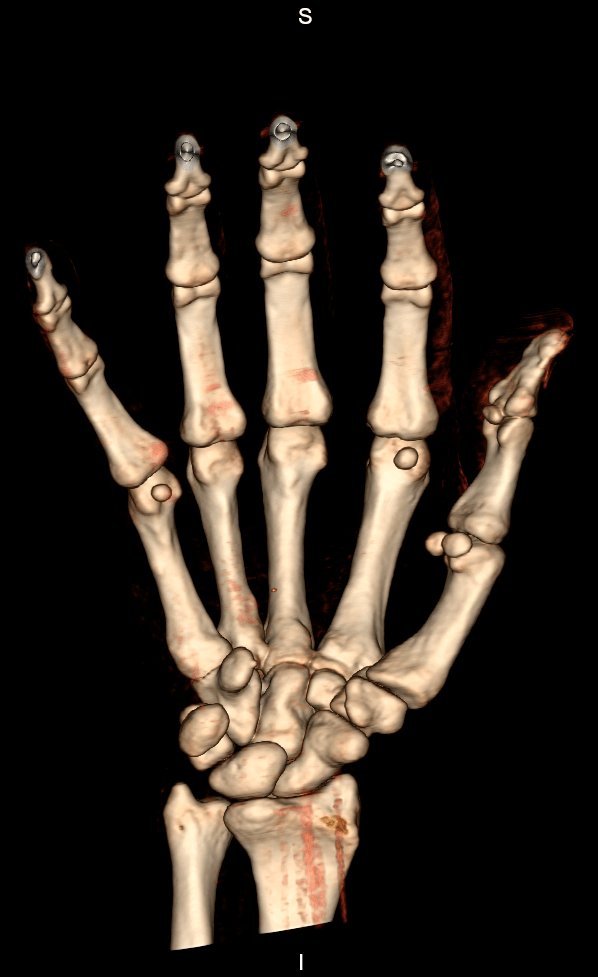

A tomografia computadorizada dos membros é um exame de imagem que serve para auxiliar o médico no diagnóstico de diversas patologias que podem afetar os membros, sendo estes divididos em:

Esse método de estudo é indicado para avaliar alguns sintomas associados aos membros, como dor ou tumefações. Permite também que sejam feitas avaliações das articulações e, sobretudo, análise do componente ósseo. É um excelente método de imagem para observar fraturas e lesões hemorrágicas. Por meio da tomografia, são realizados diagnósticos eficazes e assertivos.